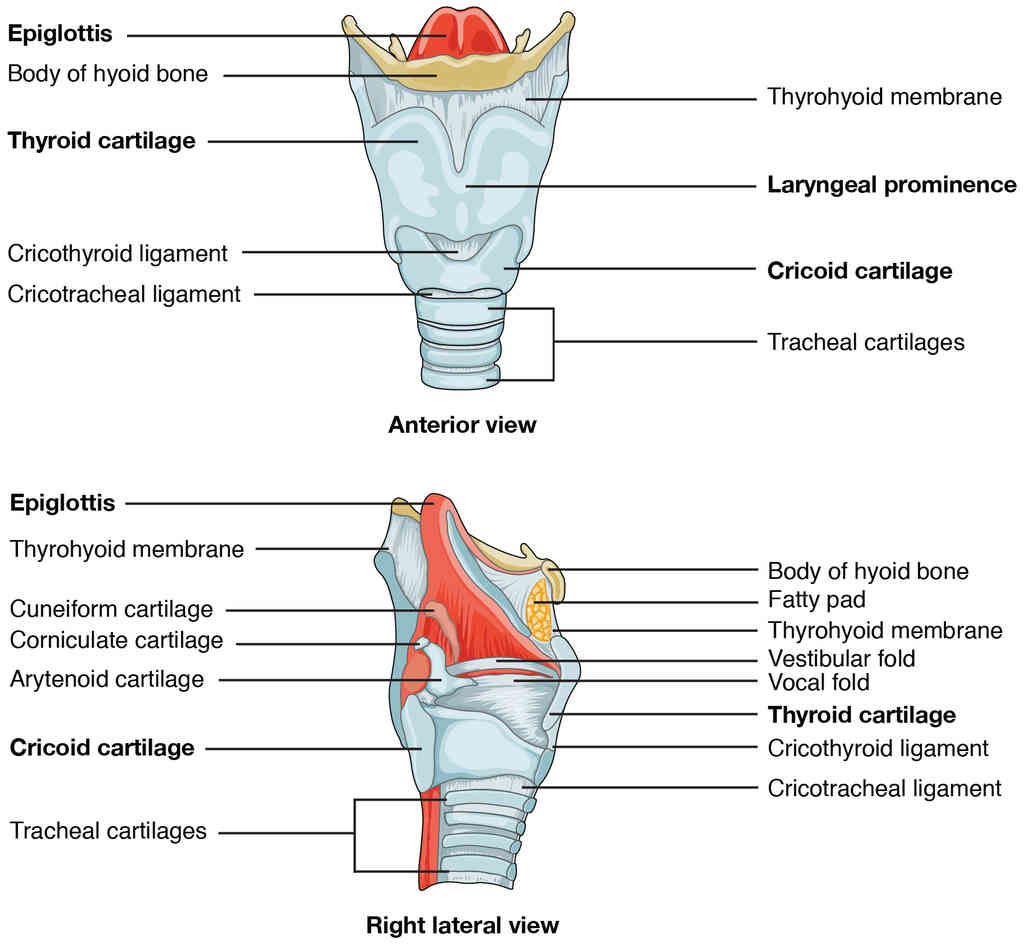

This page is under construction. For now, it is just a resource of the images found in the OpenStax Anatomy and Physiology Handbook. It wil slowly change into a revision tool. Each slide has a number. Use this to refer to the slide. When completed, it will have an unlabelled section, with labelled slides in parallel. On the unlabelled slides, write your answer and use the labelled slide to assess yourself. Keep track by also noting the number on each slide. Improvement at each attempt is important, more so than full marks on a first attempt.